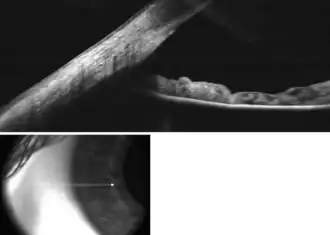

.png)